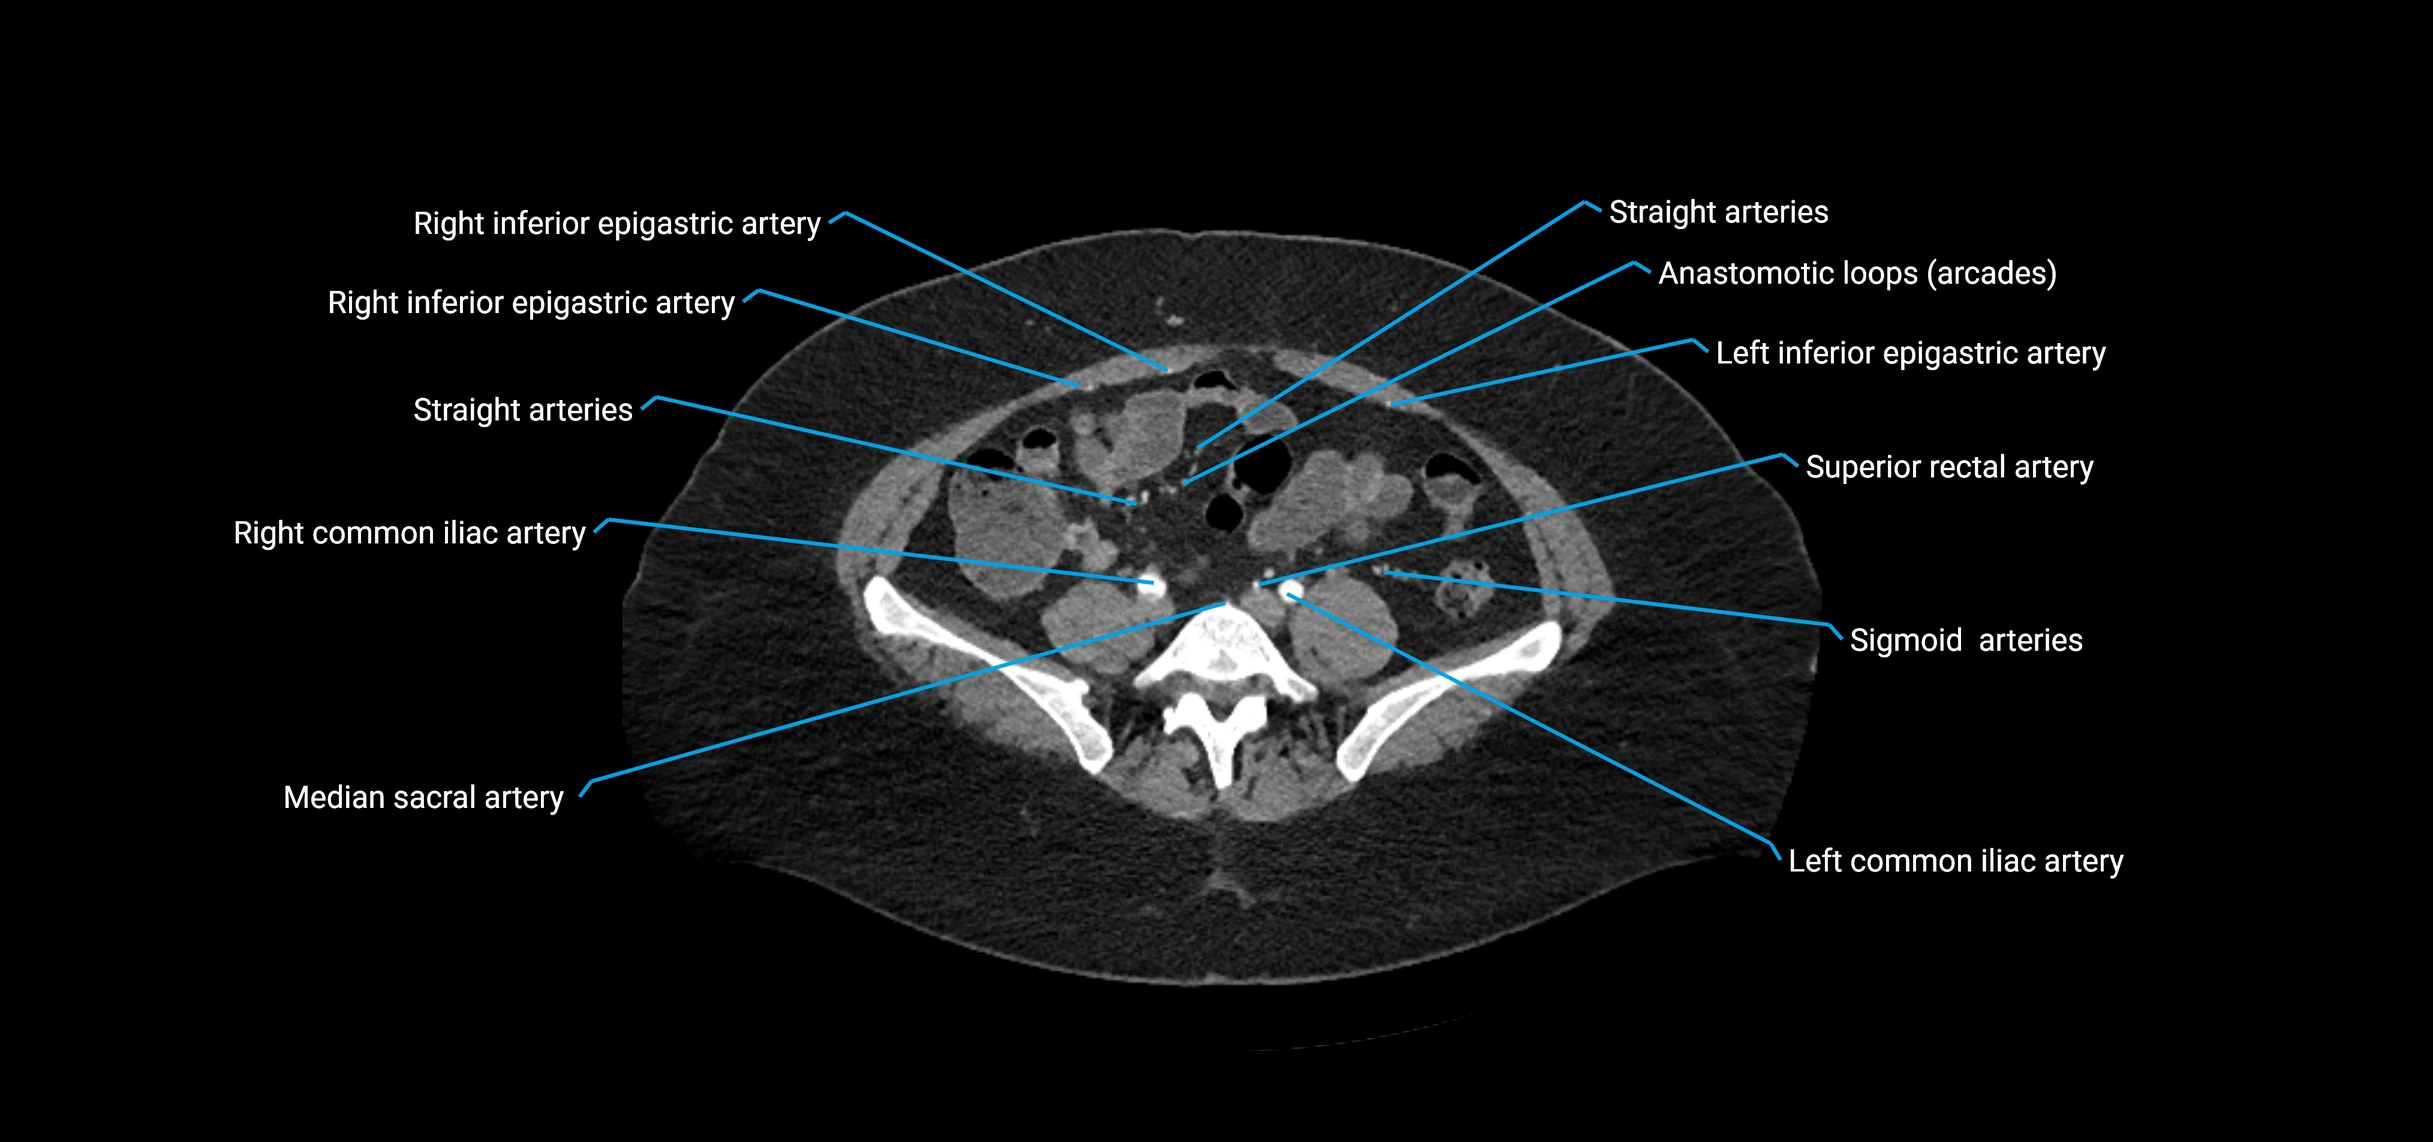

CT images

image

Contrast-enhanced CT (CTA):

• Gold standard for abdominal aortic imaging

• Provides excellent detail of lumen, wall, aneurysm, thrombus, and branch vessels

• Multiplanar and 3D reconstructions help in aneurysm measurement, stent graft planning, and dissection evaluation